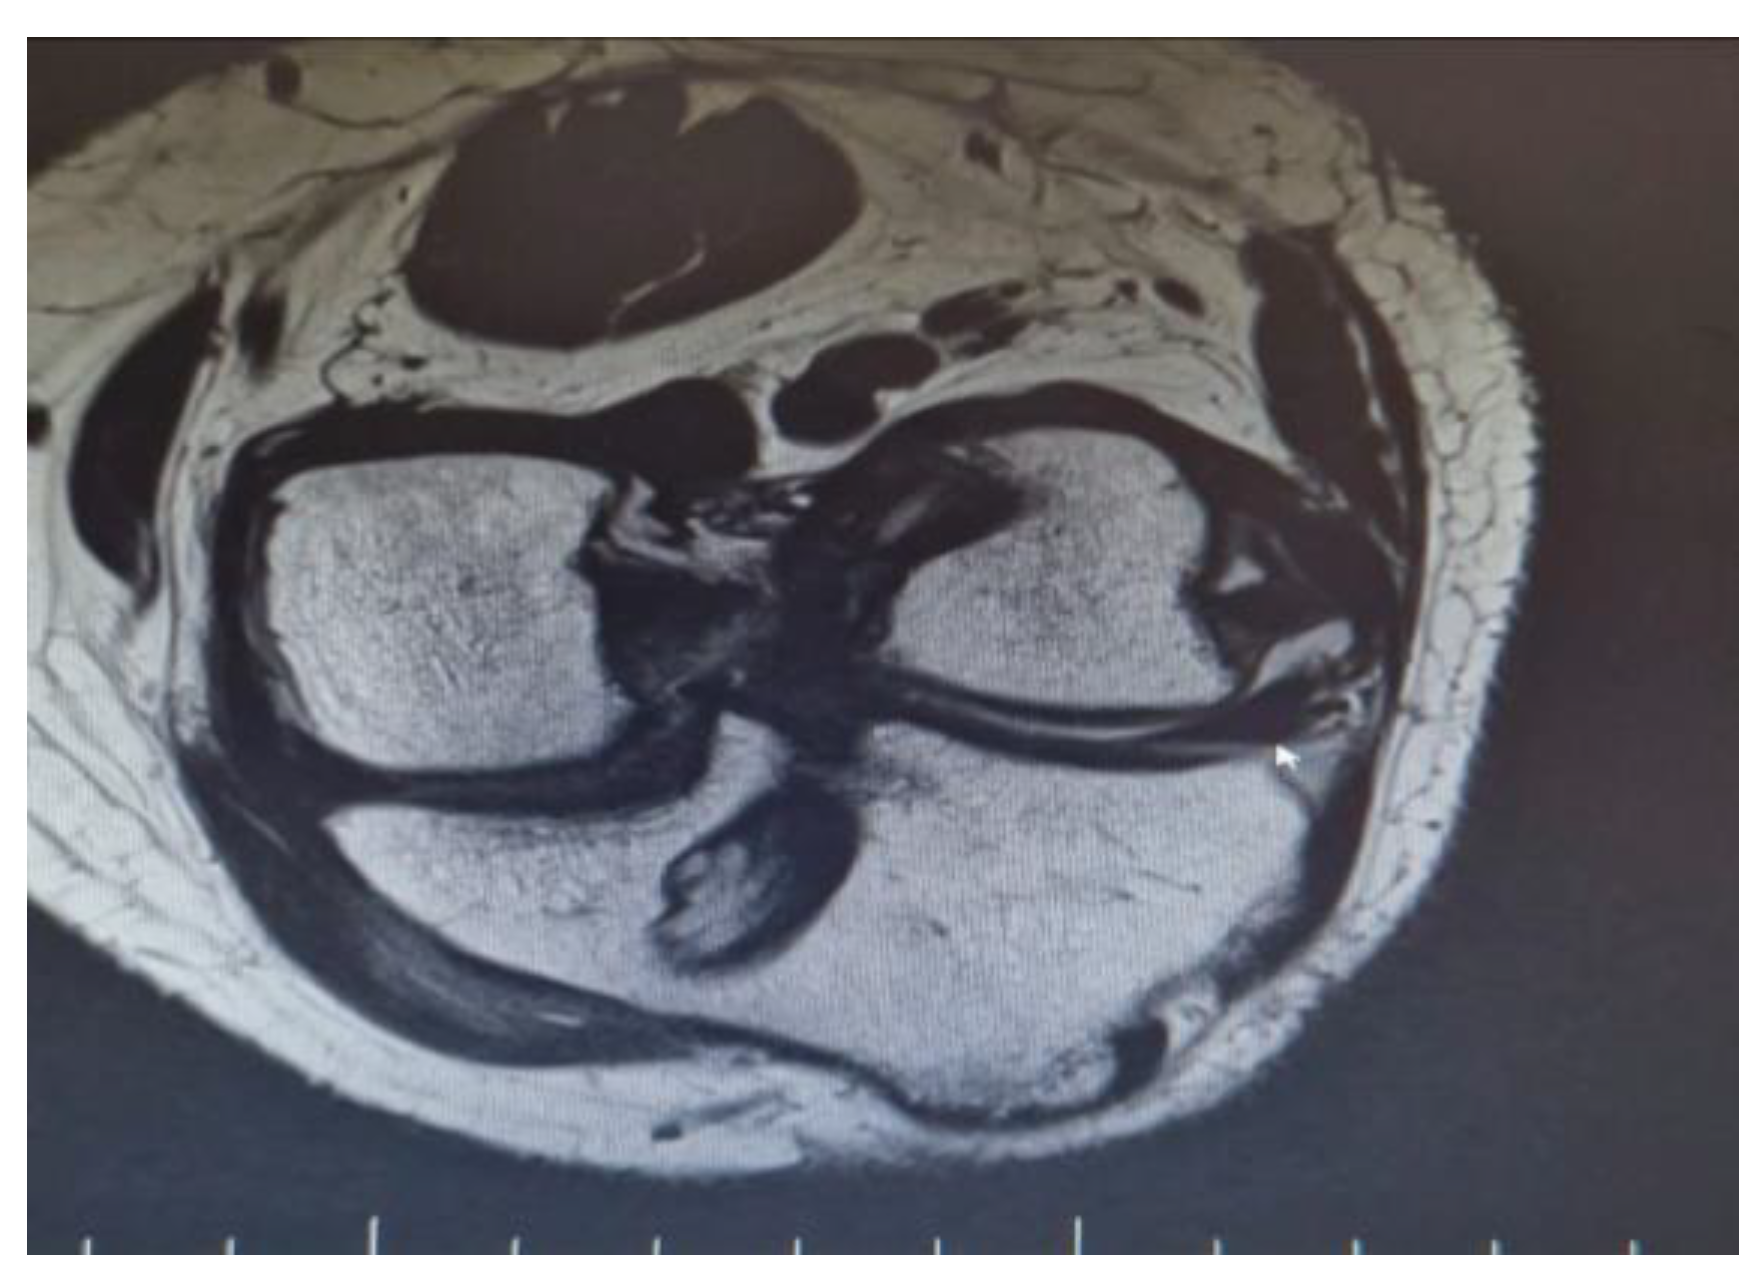

There were also a couple of cases on which a single Achilles allograft was used to reconstruct both the ACL and MCL or the ACL and LCL and ALL. In the cases where the ACL and MCL were reconstructed, the ACL was reconstructed in a standard manner, with the Achilles bone block on the femoral condyle, and after fixing the graft in the tibial tunnel, the remaining allograft was used to reconstruct the MCL. When the ACL and LCL were reconstructed with a single Achilles allograft, the femoral tunnel was created in an OUTSIDE-in technique. The ACL part was fixed with screws on the femoral tunnel and the remaining Achilles allograft was split in two, on the reconstructed LCL limb and the ALL on the other (Figure 1 and Figure 2).

Figure 1.

MRI demonstrating a single Achilles allograft used to reconstruct both the ACL and MCL, showing graft positioning and fixation.